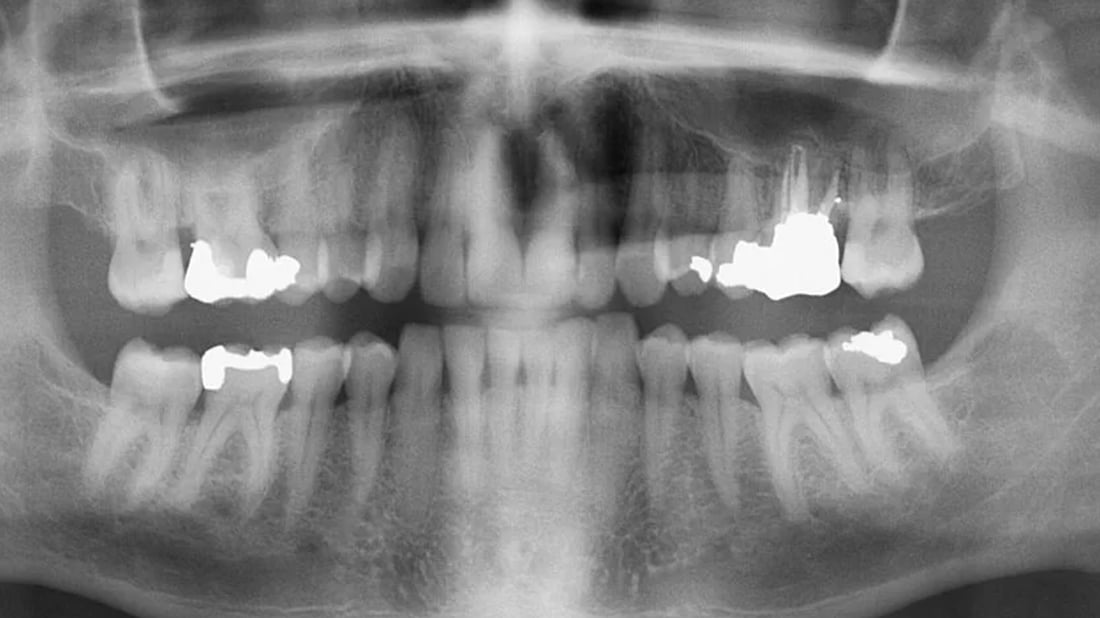

تیشکی ئێکس OPG چییە؟

بریتییە لە تیشکی ئێکس بۆ سکانکردنى پانۆرامى چەناگەى خواروو و سەروو، لەگەڵ سکانکردنى وردەکارییەکانى دیکەى ددان ئەوەش لە رێگەى وێنەیەکى پانۆرامى و پیشاندانى هەموو بەشەکانى ددان، بەوانەشى لە ژێر پوکدان و نەتەقیون بە تایبەت لە منداڵدا، ئەمەش یارمەتى پزیشک دەدات لە دەستنیشانکردنى کێشەکە.